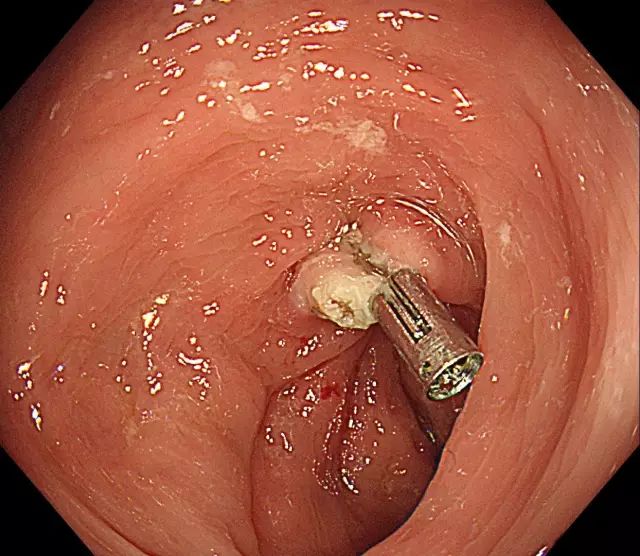

步骤六:为防止创面迟发性出血,可以使用金属夹子夹闭创面。本图为夹子在创面旁打开。

图片

步骤七:金属夹子于创面处夹闭。